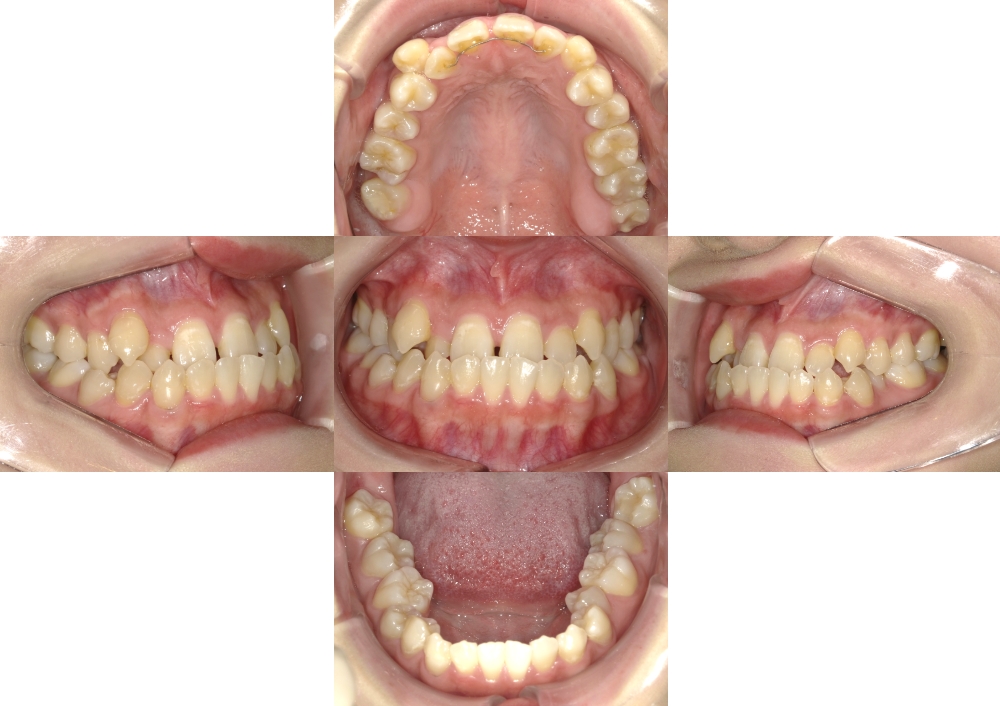

症例1

下顎前突

抜歯

ブラケット矯正

マウスピース矯正

(初診時)年齢

24歳

性別

女性

地域(住所)

日野市

主訴

受け口

診断

骨格性下顎前突、右上7番欠損

装置

マウスピース型矯正装置(インビザライン)、リンガルアーチ、マルチブラケット装置

抜歯/非抜歯

上顎両側8番、下顎両側4番抜歯(計4本)

期間

4年0カ月

費用

850,000円(税抜)(矯正装置・保定装置代込)

調整料 5,000円(税抜)×14回、 6,000円 (税抜)× 22回

症例写真

BEFORE